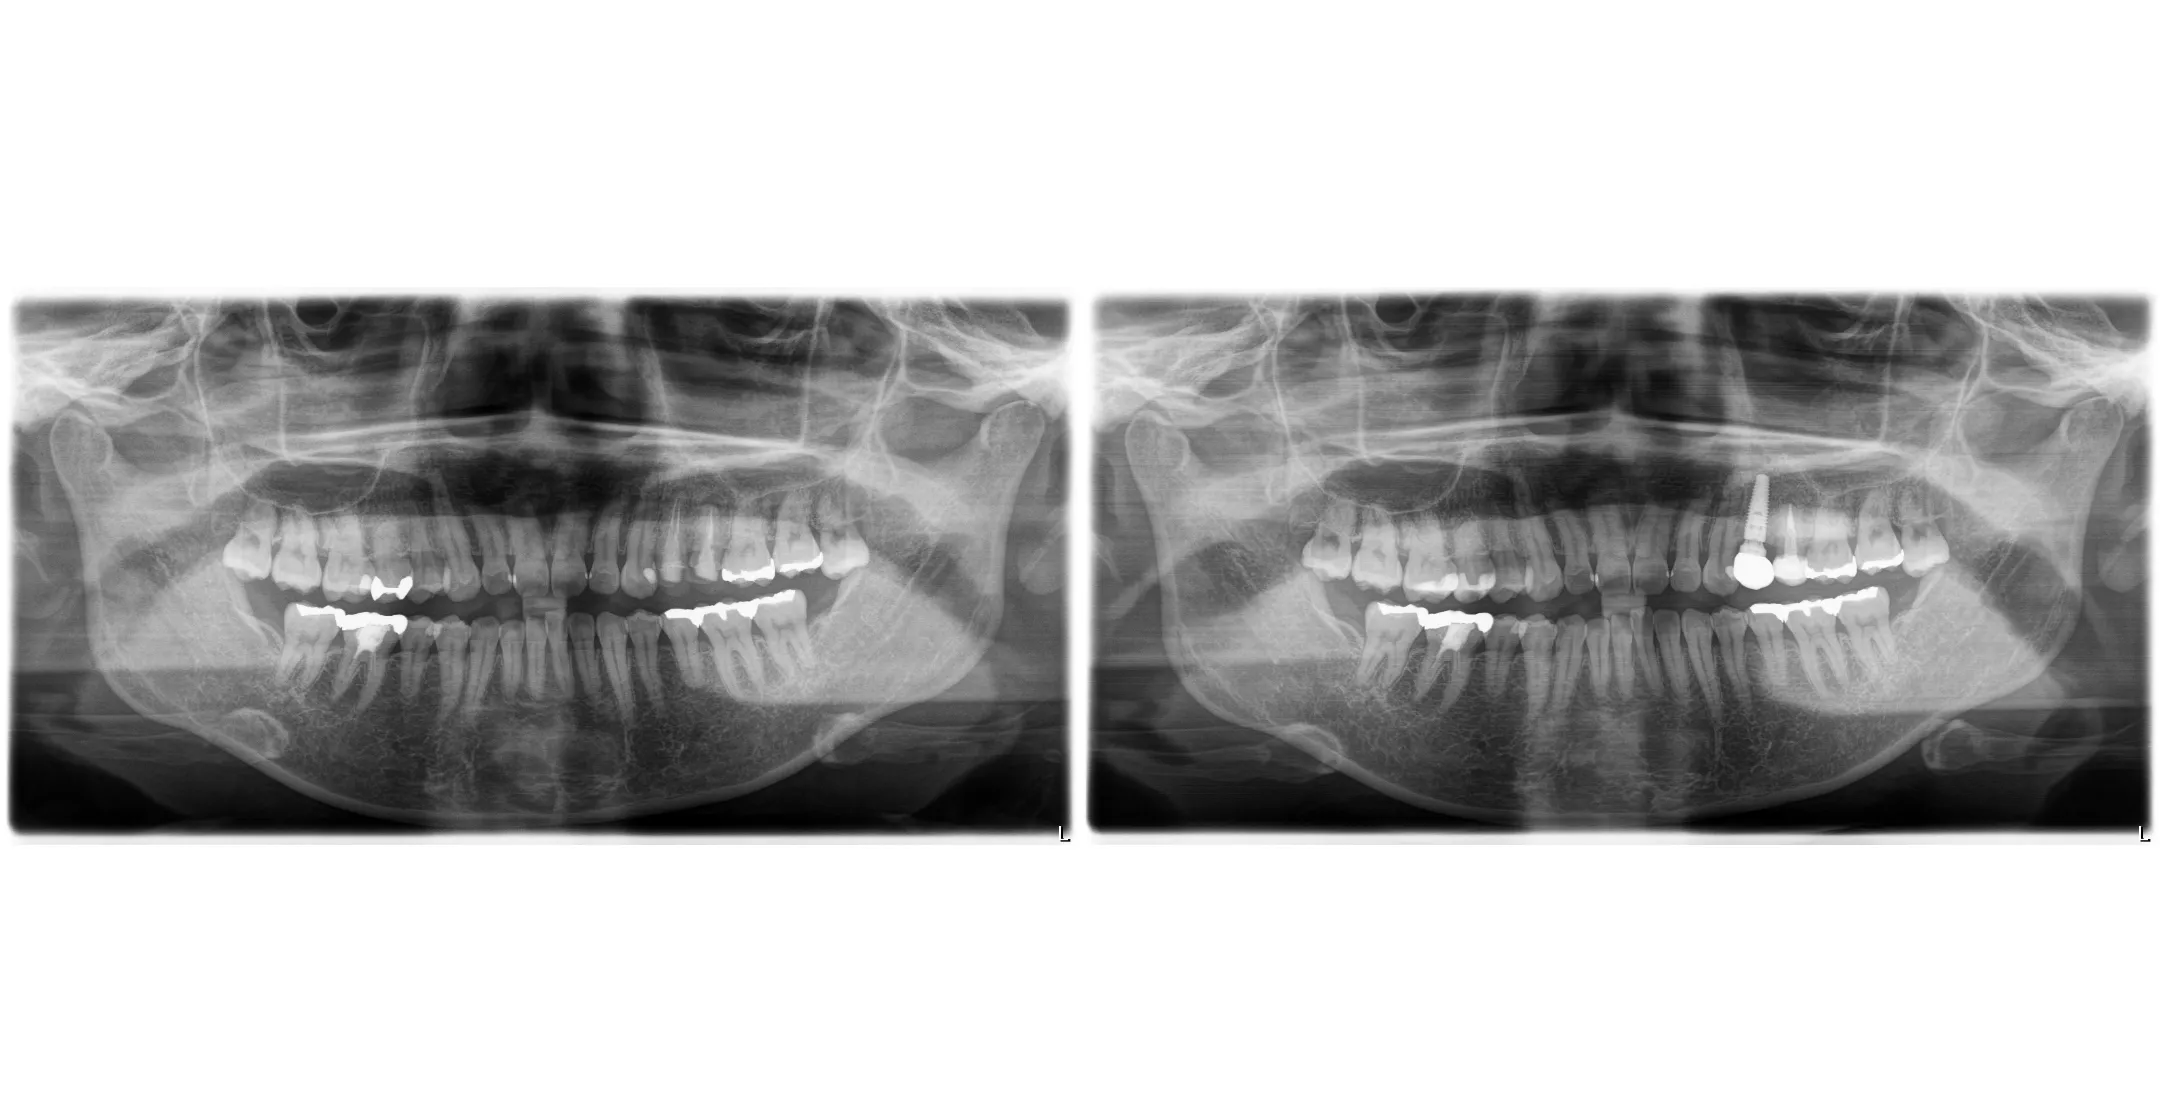

症例

【年齢・性別】 40代・女性

【主訴】 左上4、5が5年前に根っこの治療をしたが、その後左上4が2回腫れて痛い。

【期間】 8ヶ月

【通院回数】 9回

【費用】 660,000円

【年齢・性別】 60代・男性

【主訴】 左下の奥歯と右上の前歯が噛むといたい

【期間】 10ヶ月

【通院回数】 20回

【費用】 1,848,000円